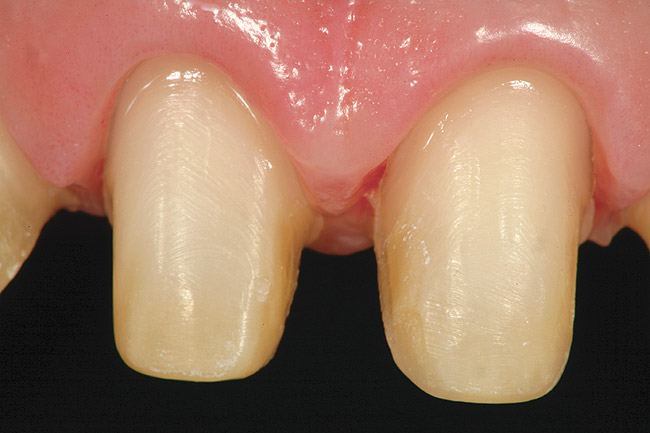

Figure 10  Facial view of the gingival tissues 9 weeks after open-flap surgery and at the time of placement of the ceramic restorations (original magnification 2x). Note the symmetrical positioning of the gingival zeniths of tooth Nos. 8 and 9. The level of tissue health 9 weeks after surgery is excellent.

Figure 10